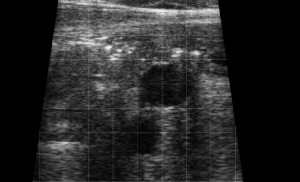

SIMON Ultrasound Database

This ultrasound database is a free resource for students and doctors!

Our collection includes videos of dogs, cats, horses, cows, humans, and many other species!